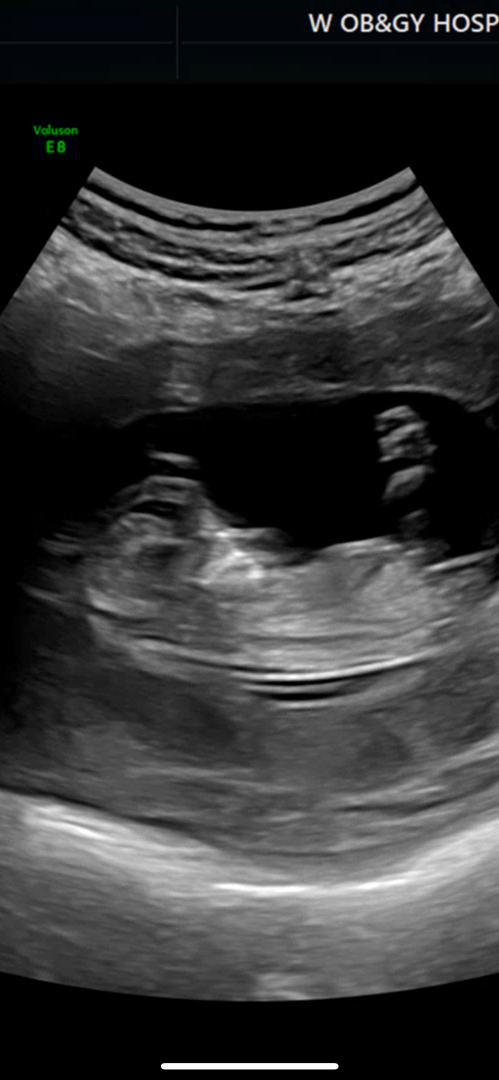

12주차 각도법 부탁드릴게용!!

각도법 봐주세용 ㅜㅜ